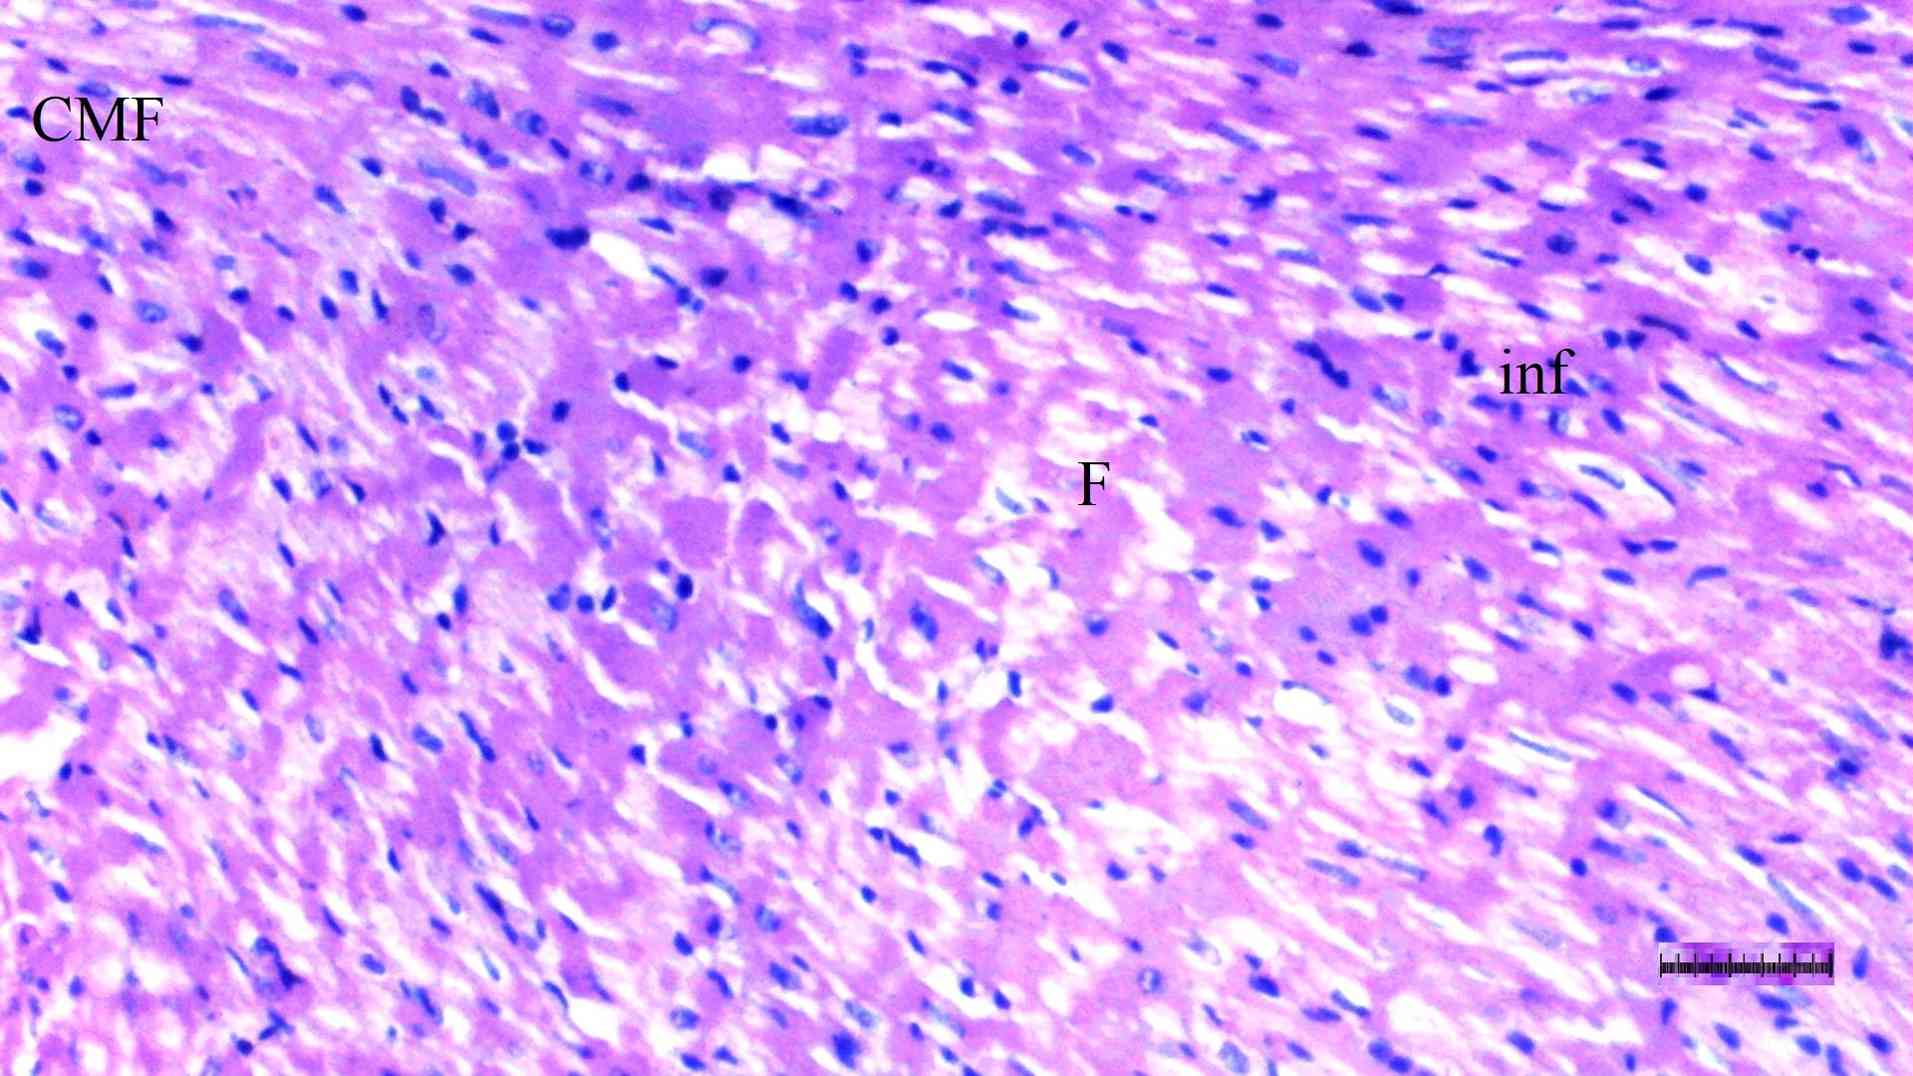

Histopathological examination of heart tissue

Inflammation varied significantly among groups (P=0.036). The DM/SEP group exhibited a significantly higher degree of inflammation compared with the S group (P=0.013) (Table II; Fig. 5, Fig. 6, Fig. 7 and Fig. 8). Interstitial fibrosis differed significantly among groups (P=0.040); it was significantly greater in the DM/SEP group compared with the S and D groups (P=0.004 and P=0.012, respectively); however, it was significantly reduced in the FUL/C-60 group compared with the DM/SEP group (P=0.040) (Table II; Fig. 5, Fig. 6, Fig. 7 and Fig. 8).

Representative light microscopy of

heart tissue from the diabetic control group. H&E staining.

Magnification, x100. CMF, cardiac muscle fibers; F, fibrosis; inf,

inflammation.

Figure 6

Representative light microscopy of heart tissue from the diabetic control group. H&E staining. Magnification, x100. CMF, cardiac muscle fibers; F, fibrosis; inf, inflammation.